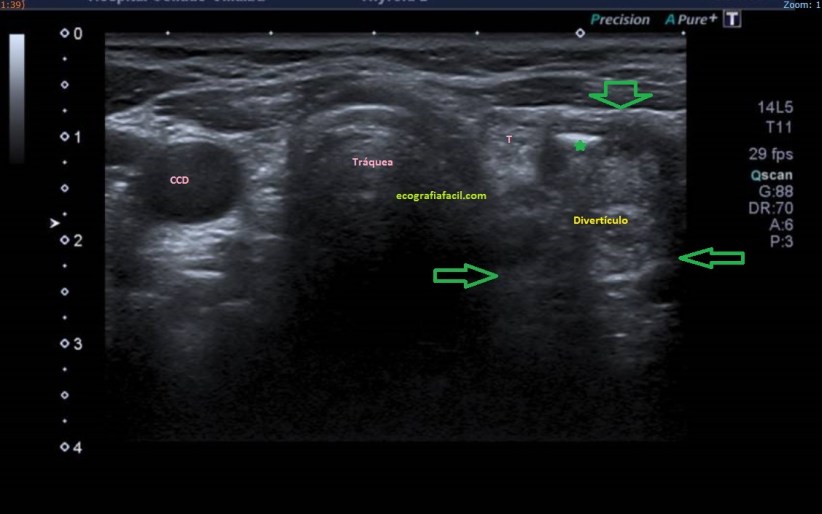

2

En la imagen 2 puedes ver el esófago, que nos vale de guía anatómica y aquí es muy importante el asterisco verde que marca el gas dentro del divertículo, en esa localización la presencia de gas es completamente anómala.

Realizamos protocolo para el estudio de cuello por ecografía y observamos que esa imagen tiene continuidad con el esófago. Tiene gas en su interior por lo que el radiólogo lo informó como probable divertículo esofágico. Este divertículo es conocido como divertículo esofágico de Killiam-Jamieson.